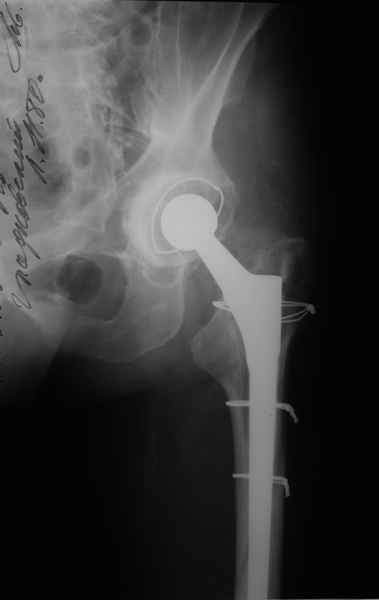

Уважаемые коллеги, продолжая дискуссию, начатую на "Вреденовских чтениях", хочу сказать, что принципиально сущестует два возможных варианта лечения.

2. Применение ножки дистальной фиксации, мы отдаем предпочтение ножке Вагнера с фиксацией проксимального отдела на ножке. Более травматичное вмешательство, но при стабильной фиксации ножки реабилитация идет в обычном режиме.

Хочется показать два подобных случая, П-ка З. 72 лет и п-т Г. 80 лет. Сразу принимаю замечание, что это были ножки цементной фиксации, просто под руками не было бесцементника.